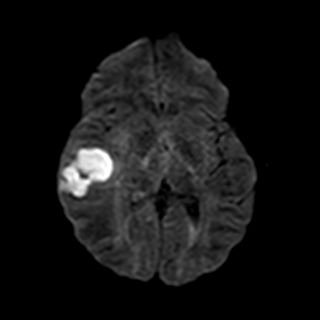

Se realiza una RM con el siguiente resultado: colección temporal derecha de aspecto polilobulado, con un eje máximo anteroposterior de aproximadamente 44 mm, que presenta marcada restricción de la difusión, así como realce parietal tras la administración de contraste. Dicha colección asocia importante edema perilesional que condiciona efecto masa sobre el sistema ventricular ipsilateral con desviación de la línea media hacia la izquierda aproximadamente 7 mm. Los hallazgos descritos son compatibles con absceso.